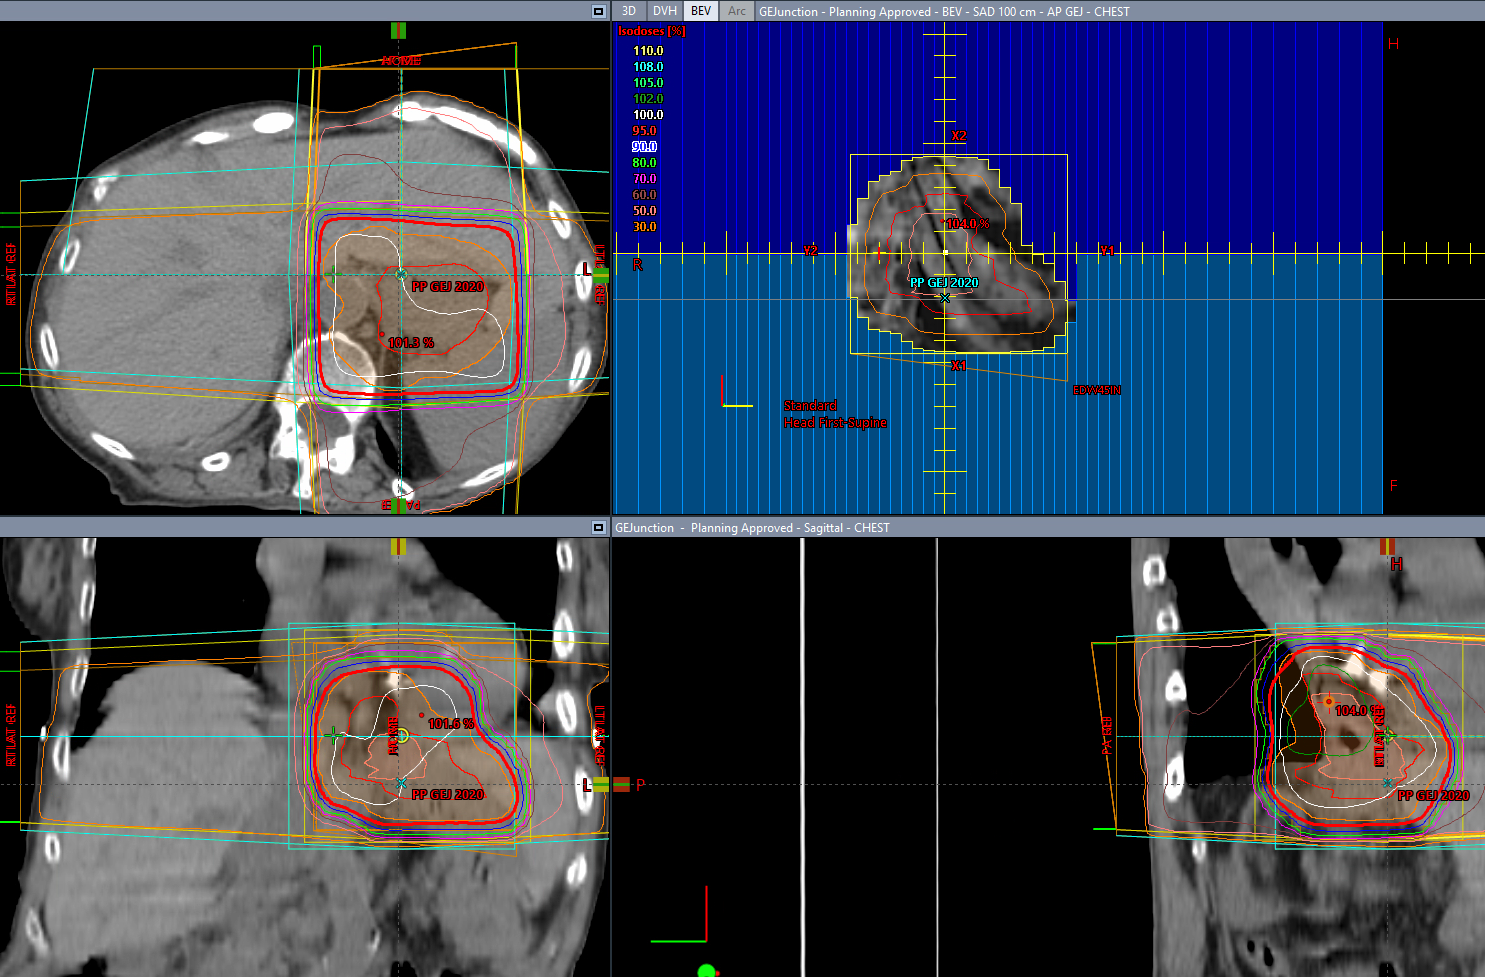

Our Intensity-Modulated Radiation Therapy (IMRT) plans are designed to deliver precise radiation doses to the tumor while minimizing dose to surrounding normal tissues. We utilize advanced optimization algorithms to create highly conformal dose distributions, ensuring optimal target coverage and organ sparing.

Volumetric Modulated Arc Therapy (VMAT) offers faster delivery times and superior dose conformity. Our team is expert in VMAT planning, balancing modulation and delivery efficiency to provide the best possible treatment for your patients.